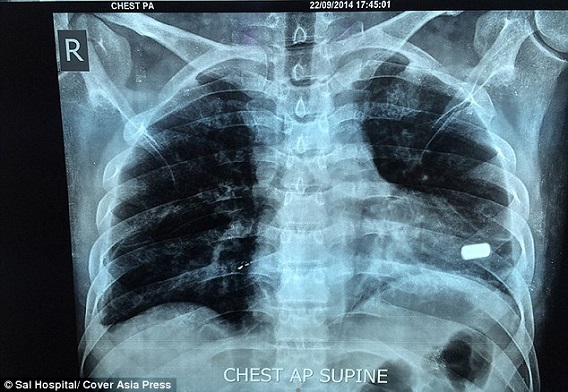

ونقل إلى المستشفى معلقاً بين الحياة والموت، وتمكن الأطباء من استخراج الرصاصة من خاصرته، فيما قرروا المغامرة بترك الرصاصة مستقرة في قلبه، لأن استخراجها في ذلك الوقت كان سيقتله في الحال.

وأذهل الهندي الأطباء حين عاد إليهم بعد شهرين لإجراء عملية جراحية بهدف استخراج الرصاصة من قلبه، إذ كان معرضاً للموت مع كل نبضة جديدة، بسبب استقرارها في الجزء الأسفل من القلب، وهي حالة نادرة جداً.

وأكد الجراح في مستشفى سال غرب الهند أنيل جاين، أن العملية الجراحية التي أجريت أول من أمس الثلاثاء، كانت بغاية الدقة والخطورة، واحتاجت إلى ثلاث ساعات متواصلة لإزالة الرصاصة التي استقرت بشكل أفقي بين الصمامين.